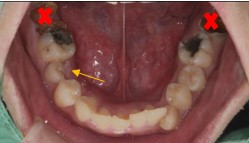

任何治療都必須做審慎評估,表面看見的問題不代表全部。 例如這位陳先生主訴是想門牙做假牙+恢復正常咬合功能。 但檢查做完之後原來沒有想像中容易,牙周/深度齲齒/根管…….等問題一一浮現,要打好基礎,有好的根基才能有穩固的建築。

治療前:前牙蛀洞大,牙齦發炎,殘根,小臼齒蛀牙深,牙齒變色。